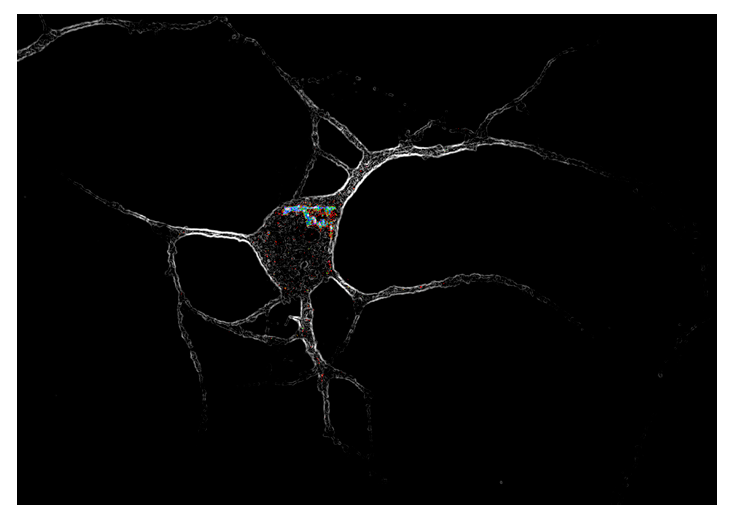

皮层神经元内表达的5-羟色胺2A受体(彩色)

通常认为,药物受体位于细胞膜表面并朝外,但这项研究显示,在神经细胞中,5-羟色胺2A受体(5-HT2AR) 集中在细胞内部,主要围绕着高尔基体结构,只有一些位于细胞表面,而同类型的其他受体则定位于细胞膜表面 。

这些研究结果表明,这些药物的作用方式存在定位偏倚(location bias) ,在细胞内激活5-羟色胺2A受体(5-HT2AR) 与在细胞外激活所产生的的效果并不相同。这项研究对于如何促进神经可塑性有了更深入的了解,有助于我们设计更好的药物 。